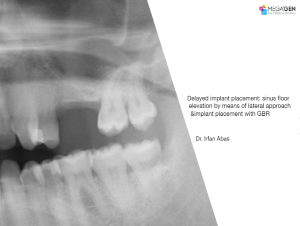

1 34 35 36